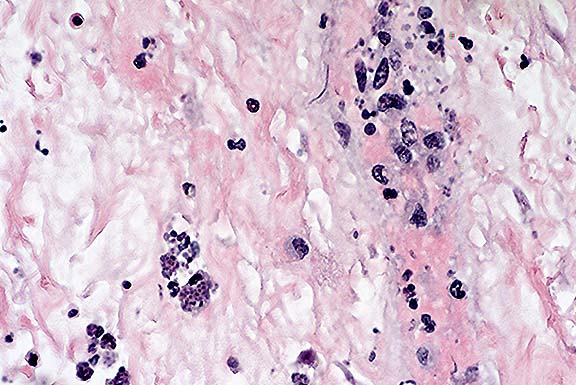

Case 8-3. Stomach. Within a vessel wall in the submucosa, there are many extracellular banana-shaped Toxoplasma gondii zoites with scattered mixed leukocytes (vasculitis). An intracellular protozoal cyst containing numerous zoites is also present (lower left). 40X

1. Stomach: Gastritis, transmural, necrotizing, acute, diffuse, severe, with necrotizing vasculitis and intracellular and extracellular protozoal zoites, Labrador Retriever, canine.

The stomach is characterized by coalescing to diffuse mucosal and submucosal necrosis with hemorrhage and marked submucosal edema. Glandular epithelial cells are pyknotic or reduced to cell debris. There is necrosis of vascular walls in the submucosa. The lamina propria and submucosa are diffusely infiltrated with neutrophils, macrophages, and fewer plasma cells. Gastric epithelial cells and smooth muscle cells contain numerous tachyzoites within the cytoplasm. Numerous extracellular tachyzoites are free within the lamina propria and submucosa, and monocytes within blood vessels contain tachyzoites. Tachyzoites associated with focal areas of necrosis were also present in liver, pancreas, adrenal gland, spleen, pancreas, lung, brain and myocardium

Disseminated toxoplasmosis is a common secondary infection in dogs that are immunosuppressed by canine distemper virus infection. However, severe gastritis with gastric signs is not usually reported. Increasingly, physicians are reporting similar gastritis due to Toxoplasma gondii in AIDS patients as a presenting complaint. Diagnosis can be made by a gastric biopsy. Both human and canine cases of gastric toxoplasmosis represent recrudescence of latent infections in immunocompromised hosts.